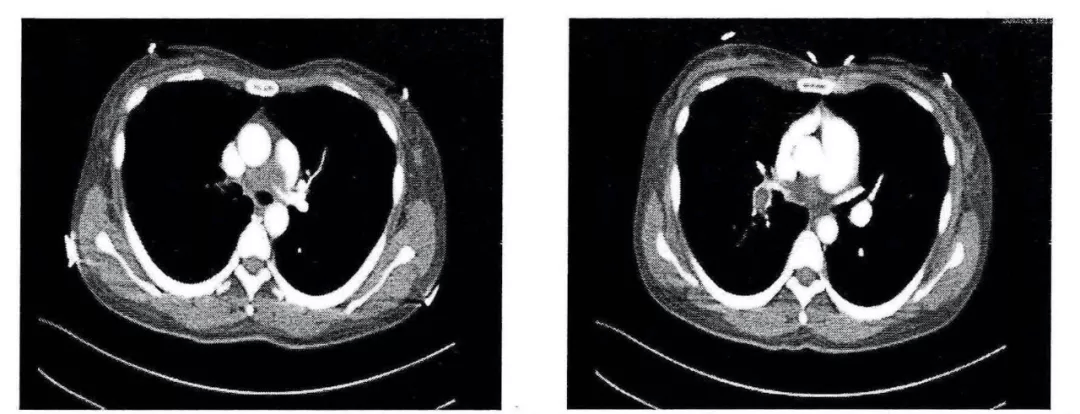

这样的充盈缺损是肺栓塞

图片尺寸1080x557

低热肺部阴影充盈缺损血栓以外还有哪些其它原因值得探寻

图片尺寸1080x871